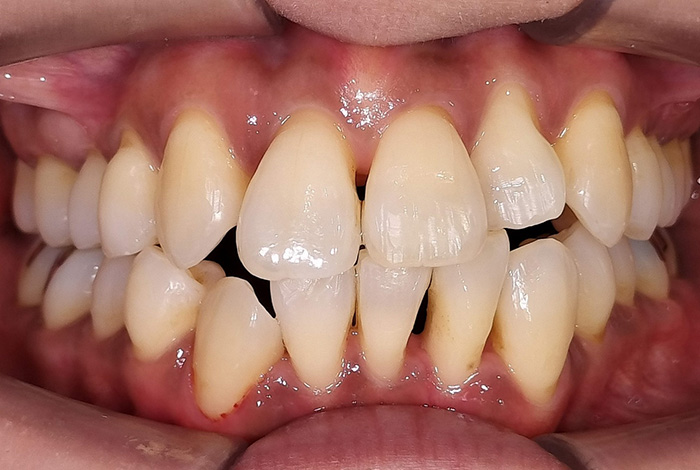

Before

前歯の見た目と噛み合わせのバランスを整えたケース

「前歯が強くかみ込んでいる気がする」「歯並びだけでなく、噛み合わせも気になる」

今回の患者様は、ディープバイト(過蓋咬合)による前歯の見た目と噛み合わせを気にされて来院されました。ディープバイトとは、上の前歯が下の前歯に深く重なっている噛み合わせのことで、見た目の問題だけでなく、前歯や顎への負担につながることがあります。

本症例では、マウスピース型矯正装置(インビザライン)を用いて治療を行いました。合計84枚のアライナーを使用し、歯並びだけでなく咬合の深さにも配慮しながら治療を進めました。

治療後は、前歯の見た目のバランスが整い、噛み合わせも改善しました。